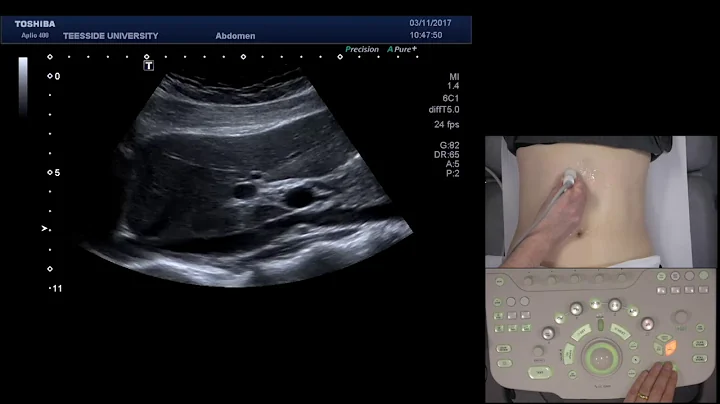

Basic Ultrasound Scanning Technique and scan windows for an Abdominal Ultrasound.